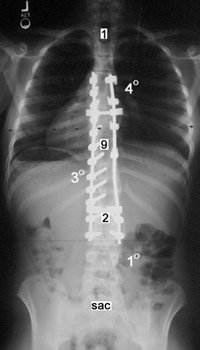

Implants consist of hooks, screws and plates, fixed on the spine. There are laminar, pedicle and transverse hooks. Screws may be monoaxial, polyaxial and cannulated. Hooks and screws are stiffly fixed by the rods, the latter fixed between them with the transverse holders. The implants are fixed with special fixing screws, some of them perform dynamometric fixation control. Implants are produced from stainless steel or titanic alloy.